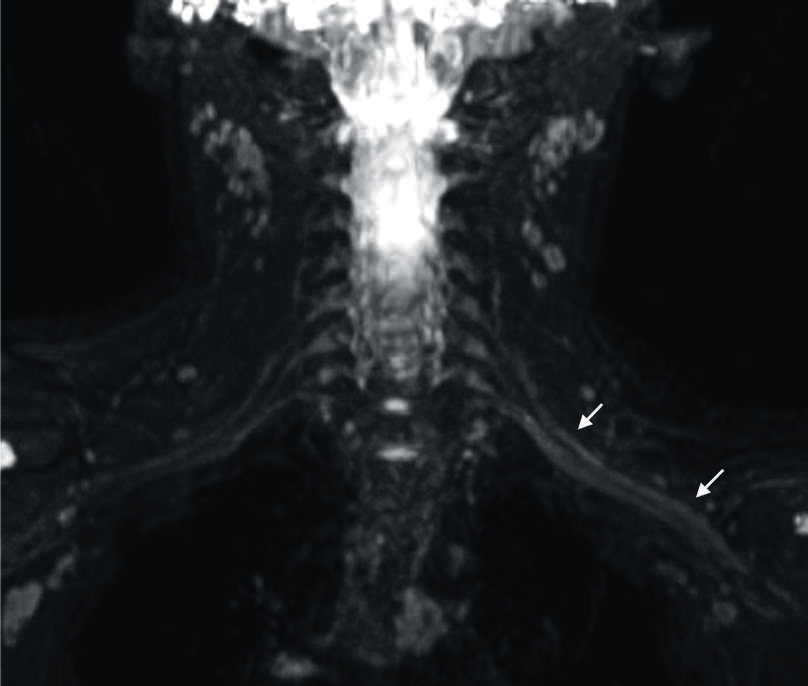

Figura 12

Sindrome de Guillain Barré en niño de 9 años

(a) Secuencia neurográfica IDEAL water en ponderación T2, que muestra engrosamiento e hiperseñal difusa de los ramos del plexo lumbar. Imagenes convencionales de columna en FSE ponderación T1 (b) axial con contraste, (c) sagital sin contraste, (d) sagittal con contraste, se observa engrosamiento y realce de raices de cauda equina.

El sindrome de Guillain Barré es la polineuropatía inmunomediada pos infecciosa más comun y es una urgencias neurológica (54). Las manifestaciones en NRM son variables en función de los nervios afectados. El hallazgo más frecuente es el el aumento de grosor y el realce pos contraste de las raíces de la cuada equina (55). Sin embargo, también se describe la afectación de plexos y con menor frecuencia de pares craneanos, los cuales se observan hipertrofiados y pueden presentar realce pos contraste. La neurografía también es de utilidad en el control de las lesiones conocidas (56). (Fig. 12).